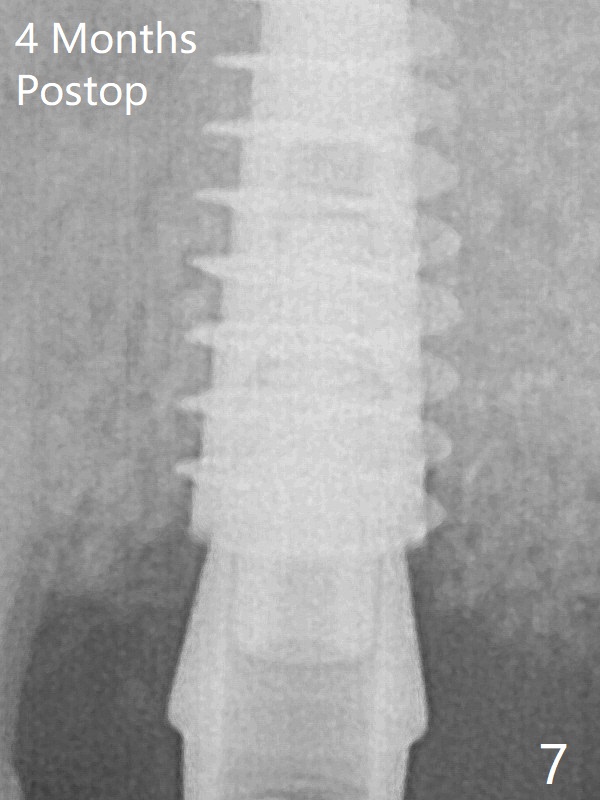

The bone graft around the abutment disappears most coronally, while that around the implant remains 4 months postop (Fig.7).  The implant is stable.